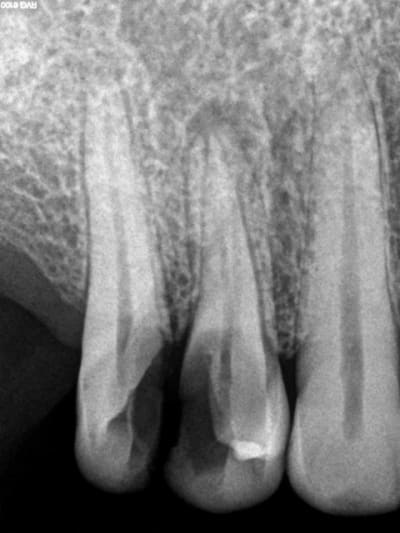

Aujourd'hui patient en urgence ca tombe bien pour une fois synchro avec un lapin.

45 mn de turbinage intensif 2 endos + 2 SC 33; On cote comment les radios ?

Z6, SC 20, Z3,Z3, SC20, Z3, Z3, SC 33, Z3, SC 33, Z3 ?